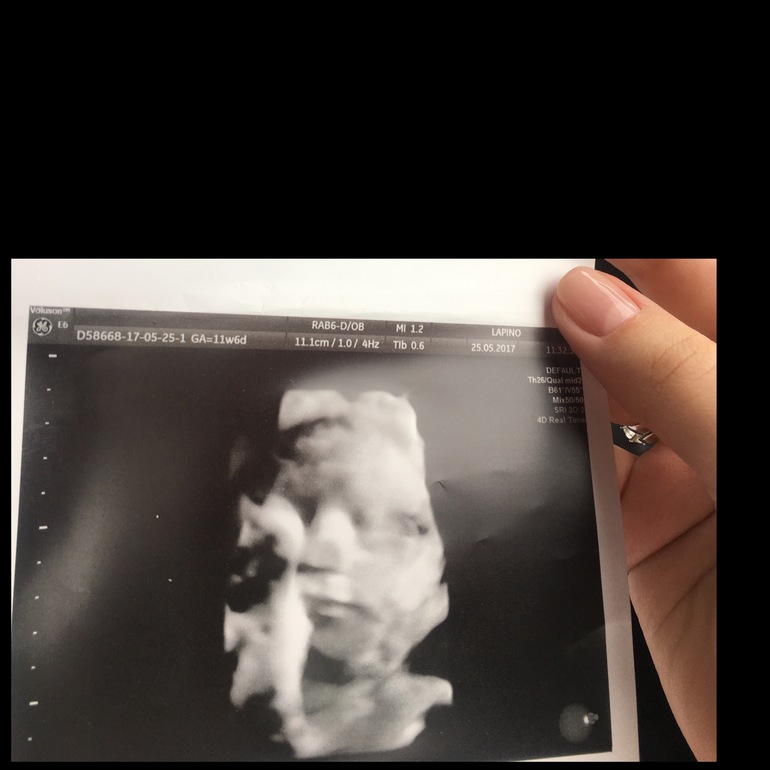

Как только поднесли датчик узи он сосал палец, и как обычно со своей ручкой закрывался) все таки моя копия))))